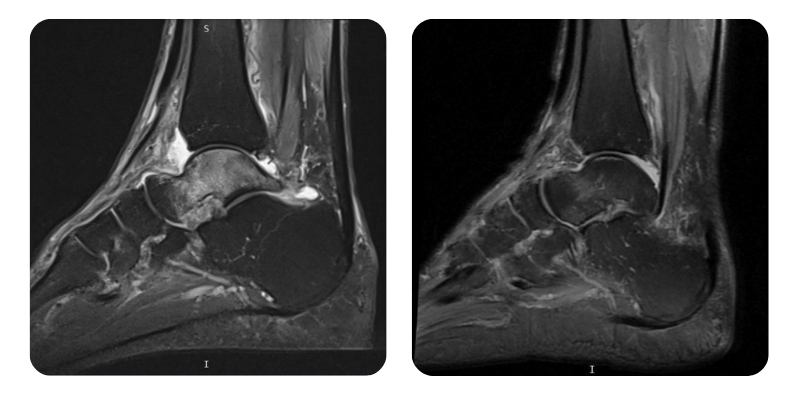

Prima

Dopo

T.F., 68 anni - Necrosi avascolare talus destro.

Anamnesi: Tre mesi fa il paziente ha riportato una frattura dell epifisi distale peroniera destra, trattata con immobilizzazione gessata. Dopo circa un mese ha avuto una distorsione della caviglia, con dolore persistente. La RMN ha confermato la presenza di necrosi asettica del talo. Ipertensione in trattamento con Preductal e adenoma prostatico.

Risultati: RMN del piede.

Diagnosi: Necrosi avascolare talus destro.

Evoluzione: L'edema e scomparso per circa il 90%.